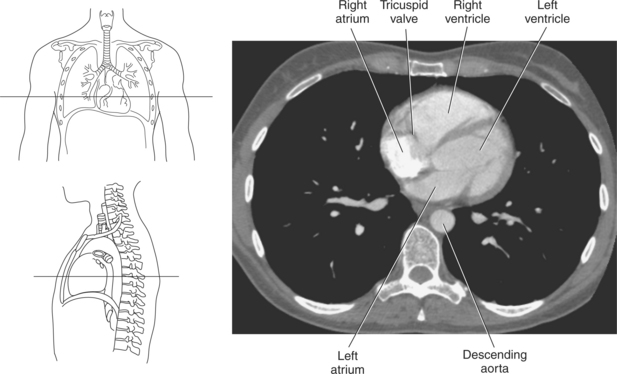

The walls of the heart consist of three layers: (1) epicardium, the thin outer layer that is in contact with the pericardium; (2) myocardium, the thick middle layer consisting of strong cardiac muscle; and (3) endocardium, the thin, endothelial layer lining the inner surface. The endothelial layer also lines the valves of the heart and is continuous with the inner lining of the blood vessels. The heart is divided into four chambers: the right and left atria and the right and left ventricles. The two superior collecting chambers called atria are divided by the interatrial septum. During embryonic development an oval opening exists within the interatrial septum called the foramen ovale. This opening allows blood flow between the right and left atria during fetal lung development. At birth, the foramen ovale closes, leaving a small depression in the septal wall called the fossa ovalis in the adult heart. The two inferior pumping chambers called ventricles are divided by the interventricular septum (Figure 6.39).

The right atrium forms the right border of the heart and receives deoxygenated blood from the body via the superior and inferior venae cavae and from the coronary sinus and cardiac veins that drain the myocardium. A small muscular embryonic appendage, the right auricle, projects upward and toward the left from the right atrium, covering the root of the aorta (Figure 6.40). The right ventricle lies on the diaphragm and comprises the largest portion of the anterior surface of the heart. It receives deoxygenated blood from the right atrium and forces it into the pulmonary trunk for conveyance to the lungs. Projecting off the inferior surface of the ventricular walls are conical-shaped projections of cardiac muscle called papillary muscles that anchor the cusps of the tricuspid valve to the right ventricle (Figure 6.39). The left atrium lies posterior to the right atrium and is the most posterior surface of the heart. It also has an embryonic appendage, the left auricle, that projects to the left of the pulmonary trunk over the superior surface of the heart. The left atrium receives oxygenated blood directly from the lungs via the four pulmonary veins (two on each side). The left ventricle forms the apex, left border, and most of the inferior surface of the heart. It receives oxygenated blood from the left atrium and pumps it into the aorta for distribution throughout the systemic circuit. The myocardium of the left ventricle is normally three times thicker than that of the right ventricle, reflecting the force necessary to pump blood to the distant sites of the systemic circulation (Figures 6.41 through 6.52). Two papillary muscles project from the ventricular walls to anchor the bicuspid valve to the ventricle (Figures 6.39 and 6.47).

Four valves are located in the heart that function to maintain one-way directional blood flow throughout the heart. The valves can be divided into two groups: atrioventricular and semilunar (Figure 6.51).

The two atrioventricular valves are found at the entrances to both ventricles and function to prevent backflow of blood between the atria and ventricles during ventricular contraction. These valves have leaflets that are attached to the papillary muscles by thin cords of fibrous tissue called chordae tendineae. The right atrioventricular valve, with three leaflets, is called the tricuspid valve, and the left atrioventricular valve, with two leaflets, is called the bicuspid (mitral) valve (Figures 6.39, 6.43, 6.44, 6.47, and 6.48).

Deoxygenated blood is brought to the right atrium from the peripheral tissues by the inferior and superior venae cavae. The right atrium contracts, forcing blood through the tricuspid (right atrioventricular) valve into the right ventricle. The right ventricle pumps blood through the pulmonary semilunar valve to the pulmonary arteries, which enter into the lungs. Oxygenated blood returns to the heart via the pulmonary veins, which enter the left atrium. The left atrium forces blood through the bicuspid (mitral) valve into the left ventricle, where it is then pumped through the aortic semilunar valve to the aorta (Figure 6.51).